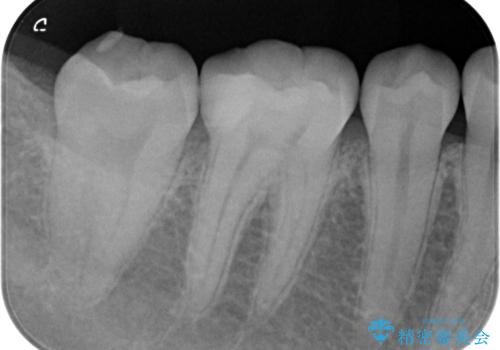

見た目ではわかりにくい虫歯ですが、レントゲン画像でははっきりと写っていました。

まだ虫歯の大きさが小さいためインレーでの修復処置を行います。

虫歯が大きくなりきる前に治療を行えたため、歯の削る量を抑えることができました。